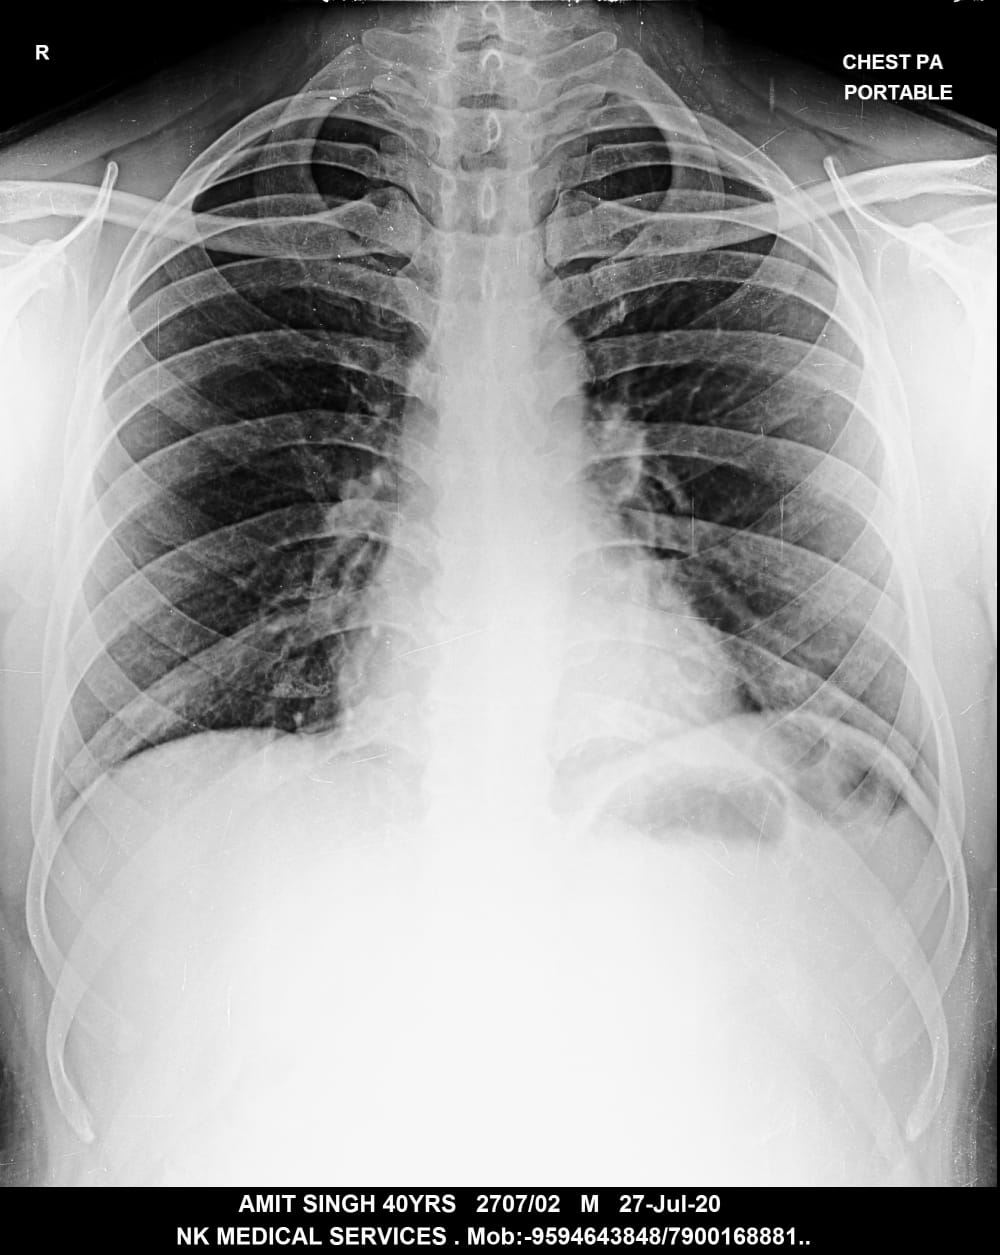

Getwell Urgent Care of Southaven uses digital X-ray technology, which uses less radiation, provides fast turnaround of images, and gives us the ability to manipulate images for more accurate readings. We follow the highest safety standards, with certified equipment and licensed radiology technologists to ensure an excellent image the first time and minimal exposure to radiation. We use digital X-ray to diagnose broken bones, certain lung conditions (e.g., pneumonia), and certain abdominal conditions.